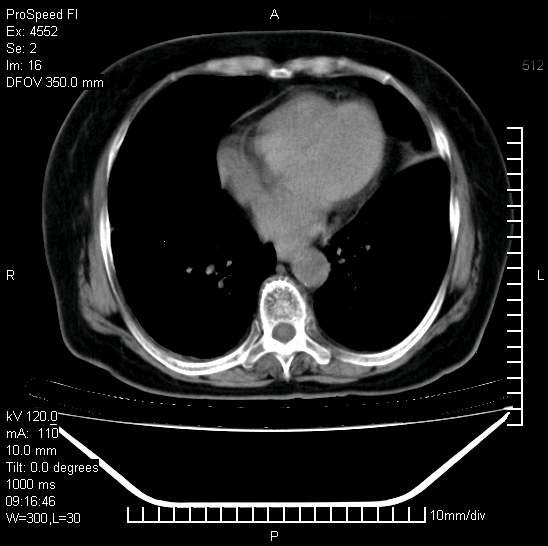

支持陈旧性肺结核并两下肺感染,两侧胸腔积液。

1)两肺结核并感染。2)不排除左肺上叶中央型肺癌并阻塞性肺炎、肺不张可能;建议行纤支镜检查。3)右肺门及纵隔淋巴结肿大。4)双侧胸腔积液。

陈旧性肺结核及左下肺不张,咯血后肺部感染,双胸腔积液,高热可能与痰液引流不畅有关。